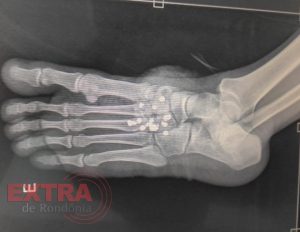

No local, os policiais identificaram a vítima como um adolescente de 17 anos. Ele relatou que possuía uma arma de fogo de fabricação caseira, tipo garrucha calibre 36, e que, ao manuseá-la, acidentalmente disparou contra seu próprio pé esquerdo.